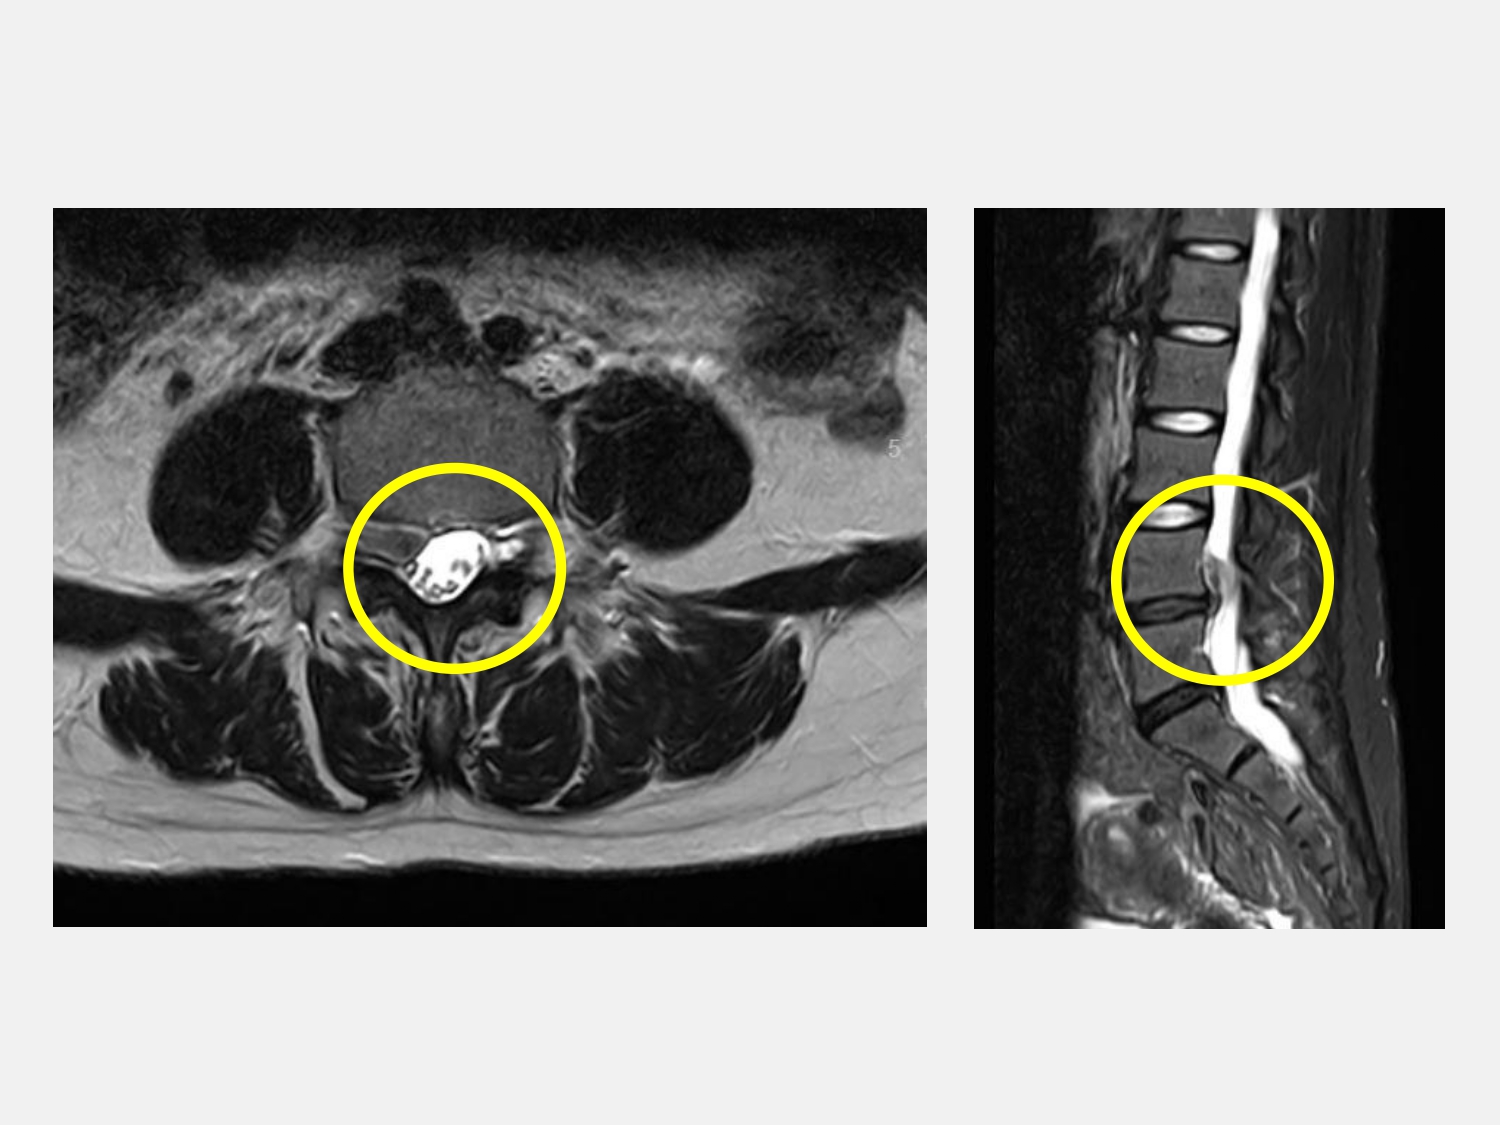

賴烱文主任為求謹慎,安排陳女士進行腰椎核磁共振(MRI)檢查,結果發現於腰椎第四第五節位置有一巨大椎間盤突出,且碎裂的椎間盤已往頭端方向游離,直接壓迫神經根,難怪保守治療效果有限。由於考量神經功能受損的風險,立即轉診至該院腦神經外科施育彤主任進一步處理。

施育彤主任接手後,詳細檢視陳女士影像,並進行神經學檢查,確認症狀與椎間盤碎裂壓迫位置吻合。施育彤主任指出,雖然陳女士經過合適的疼痛治療,但是當壓迫嚴重、神經功能開始下降時,手術介入就成為必要的選項。特別是這類游離型、往頭端移動的椎間盤碎片,常造成診斷與處理上的困難。